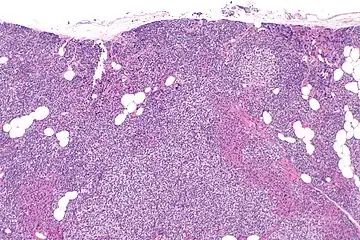

Parathyroid hyperplasia medium mag.

Primary hyperplasia of the parathyroid gland, results from both hypocalcaemia and increased phosphate levels by decreasing expression of calcium sensing receptors and vitamin D receptors at the parathyroid gland.[8][4] These decreases in receptor expression lead to hyperfunctioning of the parathyroid. Hyperfunction of the parathyroid gland is thought to exacerbate primary hyperplasia which evolves further to a secondary more aggressive hyperplasia. Histologically, these hyperplasic glands can be either diffuse or nodular.[24] Primary hyperplasia, usually resulting in diffuse polyclonal growth is manly related to reversible secondary hyperparathyroidism. Secondary hyperplasia of the parathyroid gland is more often a nodular, monoclonal growth that sustains secondary hyperparathyroidism and is the catalyst in the progression to tertiary hyperparathyroidism. Nodular hyperplastic glands in tertiary hyperparathyroidism are distinctly larger in both absolute size and weight up to 20-40-fold increases have been reported.[25][26][24]

Parathyroid glands are normally composed of chief cells, adipocytes and scattered oxyphil cells.[27][14] Chief cells are thought to be responsible for the production, storage and secretion of parathyroid hormone. These cells appear light and dark with a prominent Golgi body and endoplasmic reticulum. In electron micrographs, secretory vesicles can be seen in and around the Golgi and at the cell membrane. These cells also contain prominent cytoplasmic adipose.[27][14] Upon onset of hyperplasia these cells are described as having a nodular pattern with enlargement of protein synthesis machinery such as the endoplasmic reticulum and Golgi. Increased secretory vesicles are seen and decreased intercellular fat is characteristic.[27][24] Oxyphil cells also appear hyperplasic however, these cells are much less prominent.